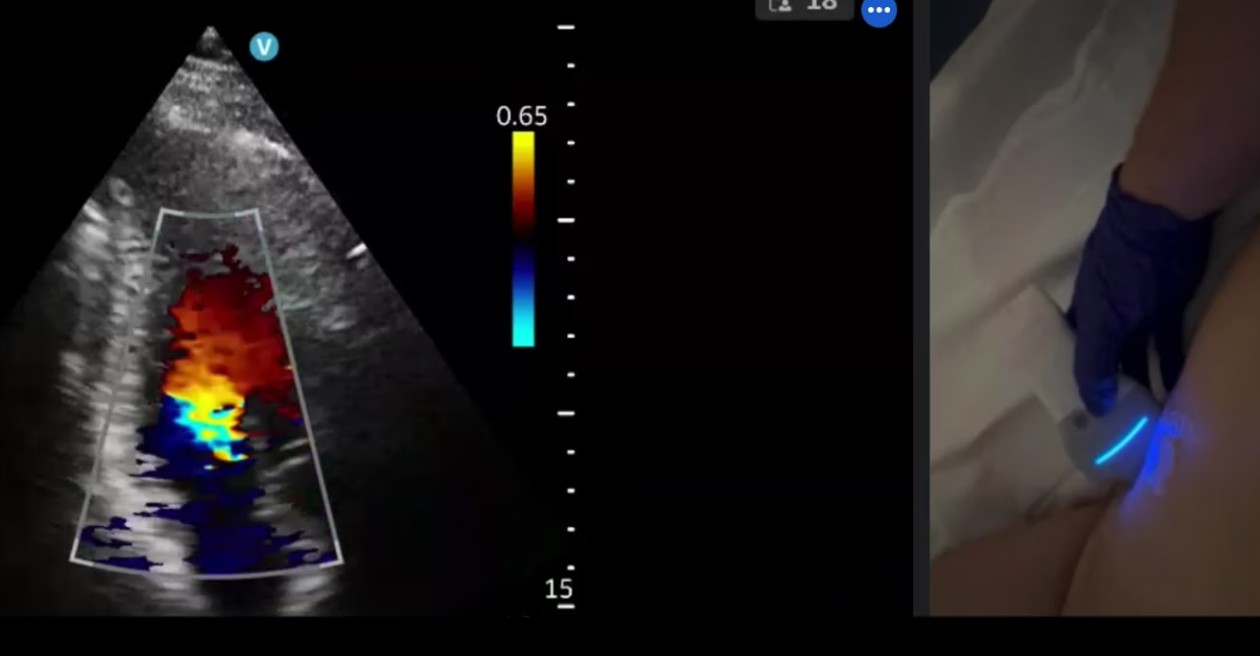

RECURSOS DIDÁCTICOS Inicio » RECURSOS DIDÁCTICOS Videos Documentos Publicaciones Casos clínicos VIDEOS Ver más DOCUMENTOS Checklist muerte encefálica Protocolos de diagnóstico y certificación de la muerte encefálica VSCAN-STROKE: evaluación ultrasonográfica con VSCAN de fuentes embolígenas cardioaórticas por un neurólogo en la fase hiperaguda del ictus isquémico Recomendaciones SONES para realizar estudios ecográficos durante la pandemia SARS-CoV-2 (COVID-19) Impacto de la pandemia covid19 en los laboratorios de neurosonologia Ver más PUBLICACIONES Estado de la neurosonología en España. Un estudio de la Sociedad Española de Neurosonología (SONES). J. Rodríguez-Pardo , J. Carneado-Ruiz, M. Martínez-Martínez, J.M. Moltó-Jordá, P. Irimia, J. Serena-Leal, Ó. Ayo-Martín, P. Martínez Sánchez, J. Pagola J. Fernández-Domínguez Supraesternal aortic debería salir del modo siguiente: Suprasternal aortic arch echocardioscopy as a potential tool in detection and follow-up of mobile thrombi in patients with ischemic stroke. Esnaola Barriola I, Escriche Gorospe E, Miguel Navas P, Martínez Campos E, Molina Goicoechea M, Capell Pascual F, Jiménez Delgado A and Muñoz Arrondo R (2025) Documento de consenso sobre técnicas neurosonológicas en cefaleas. J. Rodríguez Vico, J. Fernández Domínguez, F.J. Julián Villaverde, N. González García, C. García-Cabo Fernández, A. Jaimes Sanchez, O. Ayo Martín, J.A. Membrilla López, R.G. Martínez Martín, J. García Ull, P. Martínez Sánchez, L. Dorado Bouix, R. Belvis Nieto, P. Irimia.Neurología, 2024. Point-of-care ultrasound for transient ischemic attack assessment in transient ischemic attack clinics: Consensus document of the Spanish Society of Neurosonology. Amaya-Pascasio, L., Rodríguez-Pardo de Donlebún, J., Arjona-Padillo, A., Fernández-Domínguez, J., Martínez-Martínez, M., Muñoz-Arrondo, R., García-Sánchez, J. M., Pagola Pérez de la Blanca, J., Carneado-Ruiz, J., & Martínez-Sánchez, P. Neurología. 2024 Increased vertebral canal diameter measured by ultrasonography as a sign of vasculitis in patients with giant cell arteritis. Ayo-Martín O, Segura T et al. Frontiers in Medicine 2023 Transcranial sonography in atypical parkinsonism: how reliable is it in real clinical practice? A multicentre comprehensive study. Alonso Cánovas A, Tembl Ferrairó JI, Martínez-Torres I, López-Sendón Moreno JL, Paree-Moreno I, Monreal-Laguillo E et al. Parkinsonism related disorders 2019; 68: 40-45 Qué debería saber el médico de familia sobre la ecografía transcraneal en neurología. Fernández Domínguez J. FMC 2016; 23 (8): 467-473 Evaluación de la sustancia negra mediante ultrasonografía transcraneal. Vivó-Orti M, Tembl JI, Sastre-Bataller I, Vázquez-Costa JF, Sahuquillo P, Burguera JA. Rev Neurol 2013; 56 (5): 268-274 Utilidad del duplex orbitario para la valoración de atrofia del nervio óptico en enfermedades desmielinizantes: estudio piloto. Fernández-Domínguez J, García-Rodríguez R, Mateos V. Rev Neurol 2012; 54 (10): 587-592 Dúplex transcraneal en la enfermedad de moyamoya. Vázquez-Sánchez F, López-Veloso M, Argandoña-Palacios L, Segura T. Rev Neurol 2012; 54 (2): 249-250 Ver más CASOS CLÍNICOS Caso 7 – 2023 Ver caso Ver todos los casos SONES SOCIEDAD ESPAÑOLADE NEUROSONOLOGÍA secretariasones@gmail.com HAZTE SOCIO ¡Síguenos en Twitter!